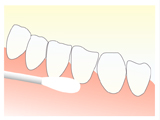

STEP1 表面麻酔

無痛治療を行うために、表面麻酔薬を麻酔を打つ部分に塗ってから麻酔の針を挿入します。表面麻酔の効果により針を刺す際のチクッという痛みを防ぐことができます。